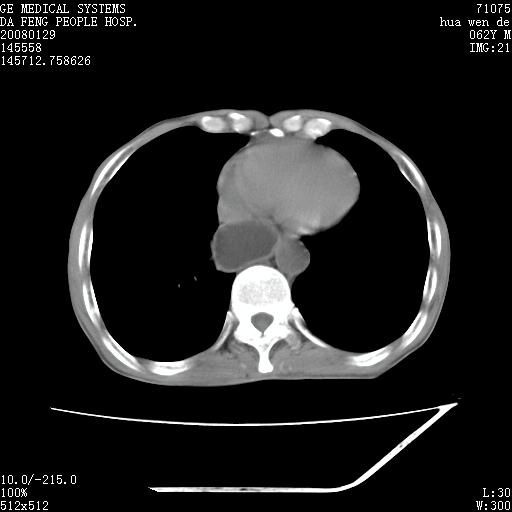

男性,67岁。作肺部检查时发现

右肺脓肿 胸腔胃

考虑1、右肺周围型肺癌可能性大。

2、贲门失迟缓症可能,建议钡餐检查。

考虑:胸腔胃并支气管瘘(并发肺炎,肺脓肿形成)。

理由:1、右上肺内病灶,空洞形成,有液平。

2、肺内多处炎症。

3、前段肺内炎症,支气管引流通畅,与肿块无关系。

1.整个食管扩张,未见明显占位性病变,贲门区亦未见明显占位病变,考虑:贲门失驰缓症;

2.右上肺病变边缘可见毛刺,囊壁厚度不均匀,周围境界较清楚,未见炎性渗出性影,右上肺外带可见片状影,边缘不清,考虑:肺癌伴空洞形成、右上肺炎。

食管全程扩张,壁均匀不厚,喷门失弛缓症

右上肺空洞可见液平,临近肺野磨玻璃密度,考虑1.结核2.脓肿